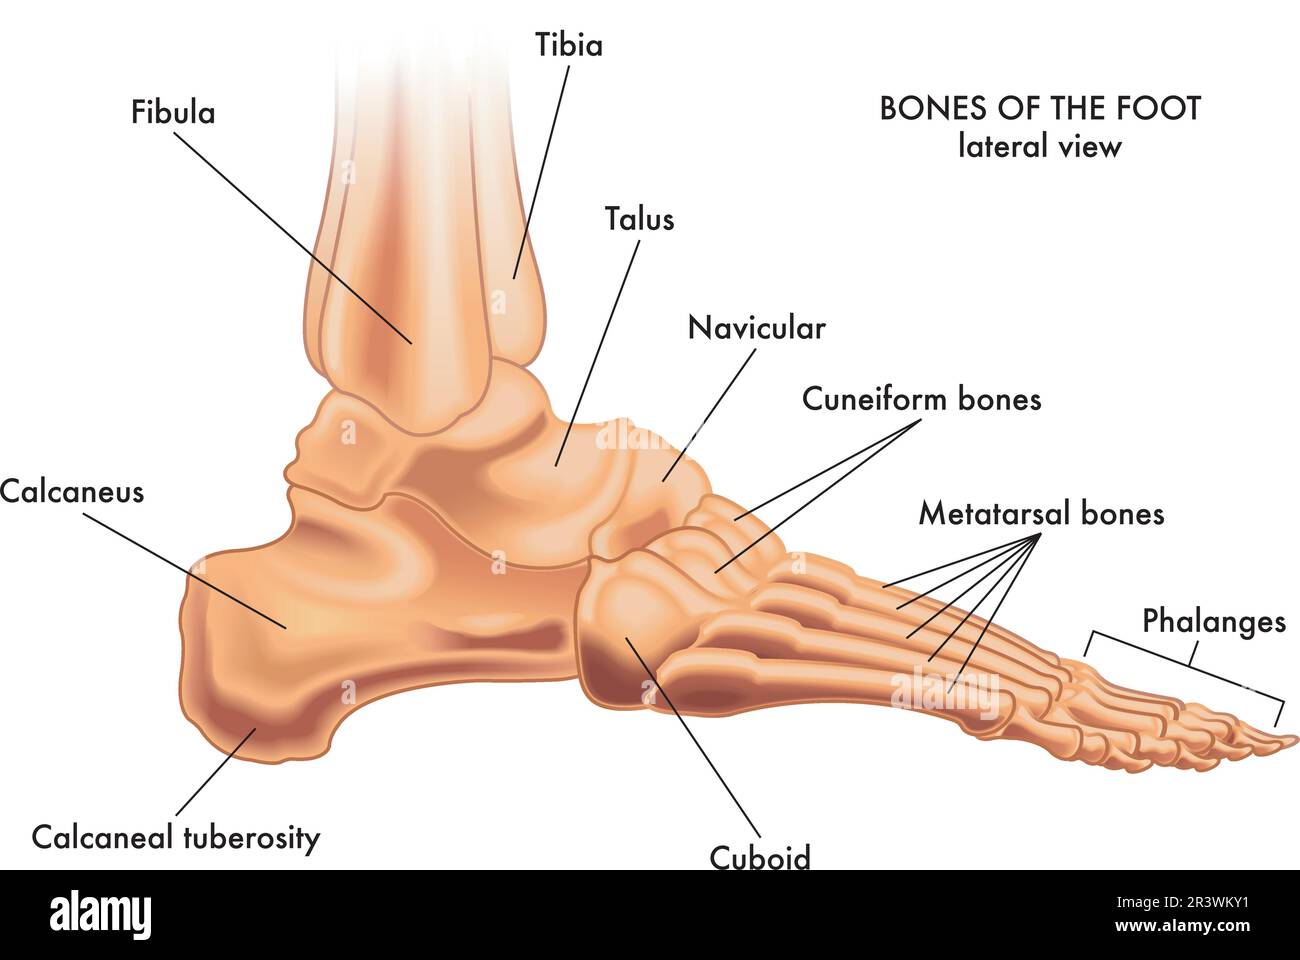

RF2R3WKY1–Illustration médicale des principales parties des os du pied en vue latérale, avec annotations.